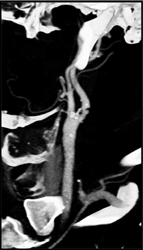

Carotid Stenosis and Plaque